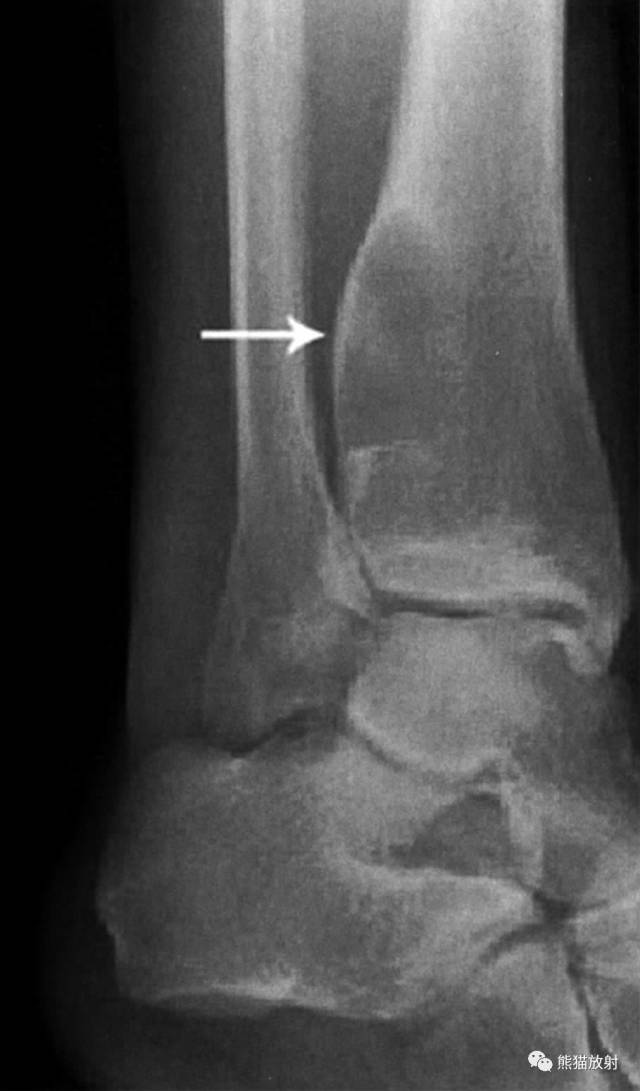

↓ 肱骨上段纤维结构不良并病理性骨折(男23岁)